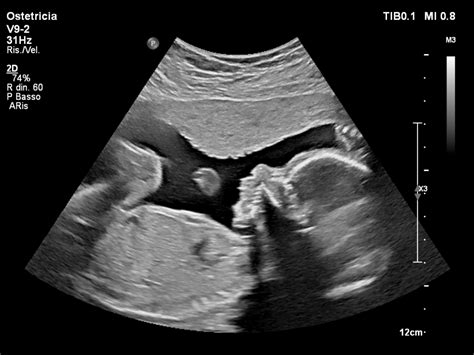

Un altro segno che deve mettere in allarme è la mancata espulsione di un cucciolo per più di 2 ore da quello precedente. Tenete sempre sotto controllo i fluidi fetali quando si rompono le acque, in quanto, se il fluido di colore verdastro o qualsiasi altro scolo dura più di due ore senza che accada nulla in seguito, non è fisiologico e non è normale se vedete uscire dello scolo di colore verdastro per più di 2 ore senza fuoriuscita di annessi o cuccioli. Se si evidenzia un ritardo di oltre 24 ore rispetto alla data del parto (determinata mediante l’ovulazione), si consiglia fortemente un accertamento ecografico dello stato di salute dei feti.